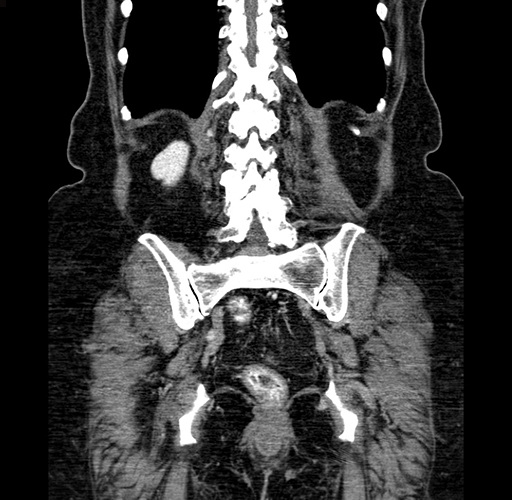

Coronal Venous